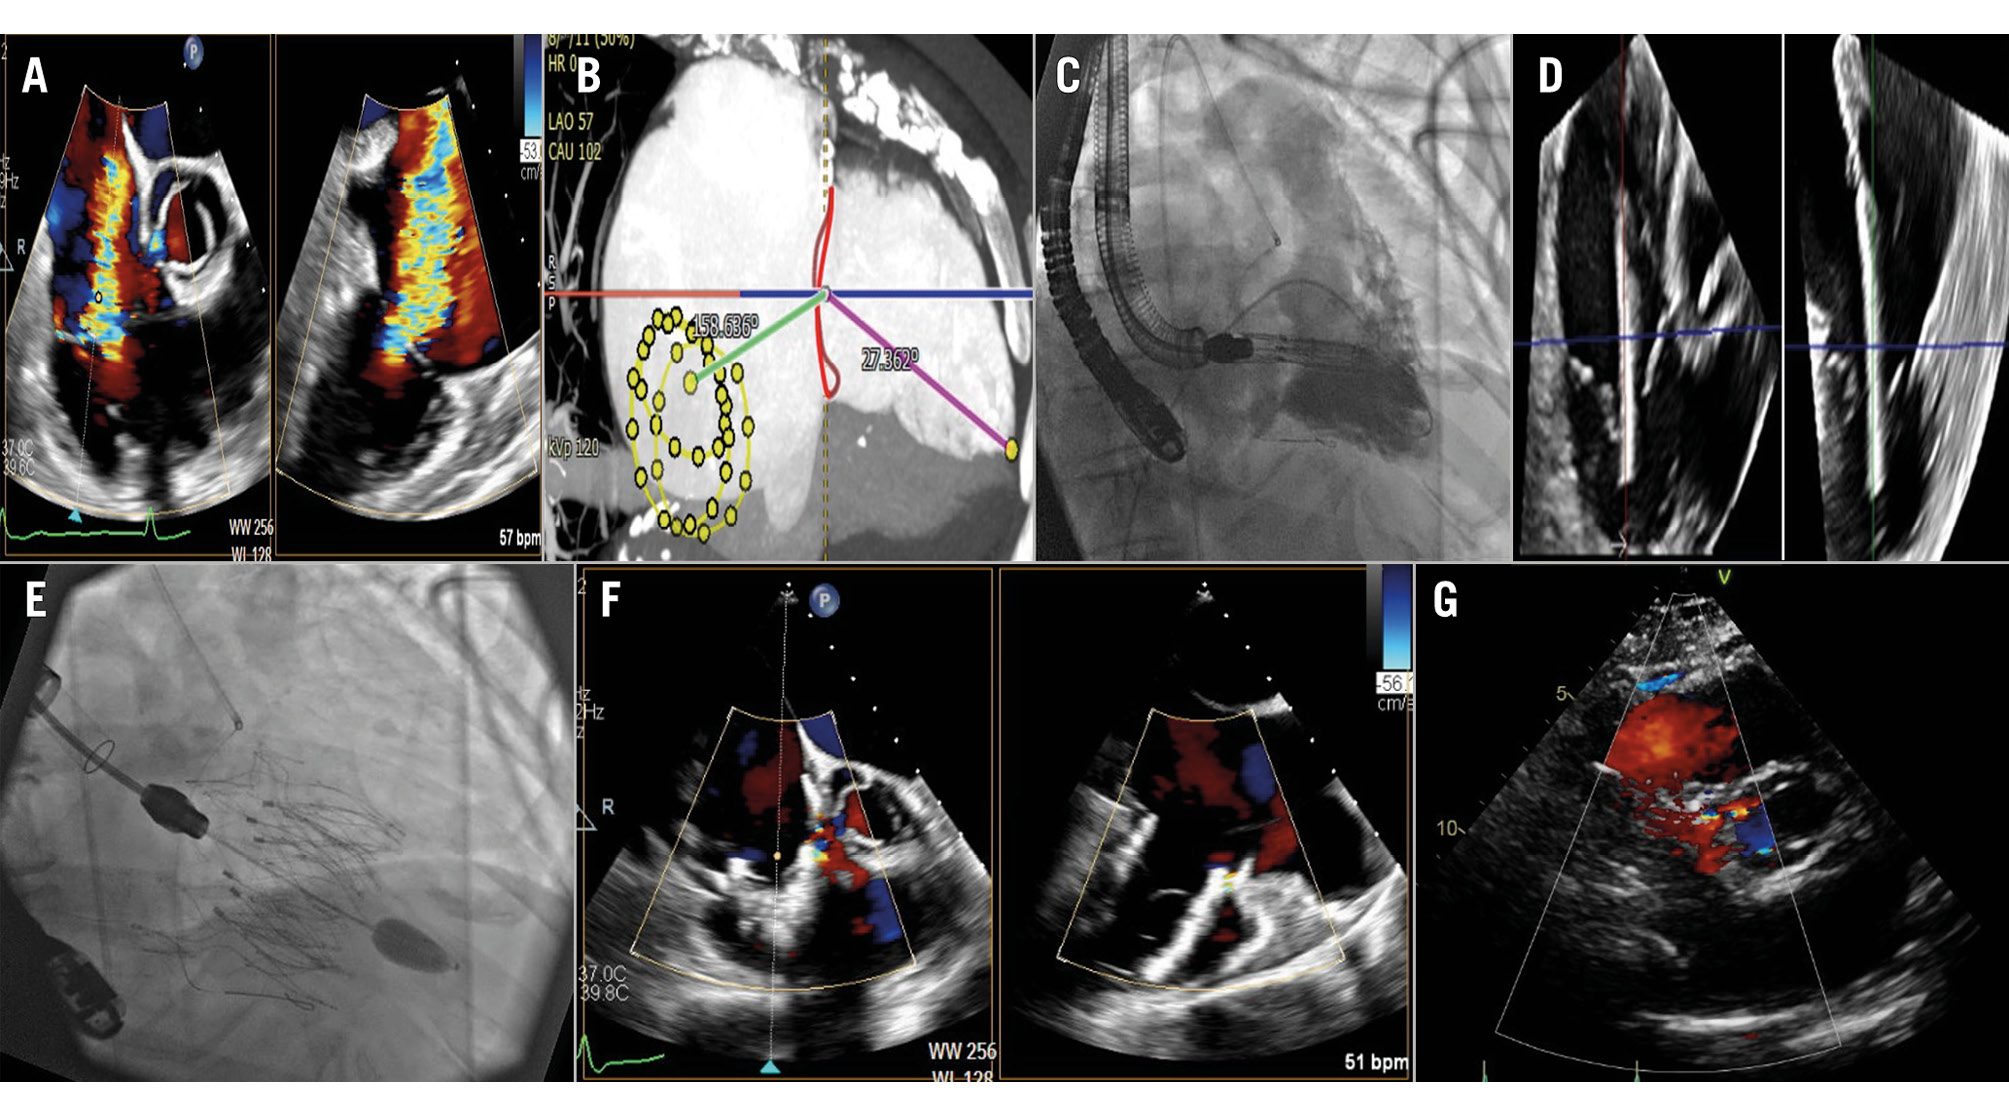

A 74-year-old female with severe tricuspid regurgitation (TR), New York Heart Association Class III dyspnoea, oedema, and fatigue was referred for transcatheter tricuspid valve intervention. Past medical history included atrial fibrillation, hypertension and diabetes. Echocardiography demonstrated torrential TR due to a large malcoaptation gap and multiple scallops, with preserved right ventricular function (Figure 1A, Moving image 1). Computed tomography (CT) imaging revealed a tricuspid annular area of 12.7 cm², with significant offset between the inferior vena cava (IVC) and tricuspid annulus, precluding coaxial valve delivery via the femoral approach (Figure 1B). After Heart Team review, she underwent transcatheter tricuspid valve replacement (TTVR) using a 45 mm Topaz device (TRiCares)1 via the transjugular approach. After percutaneous right internal jugular venous access, an Agilis steerable sheath (Abbott) was used to place an extra small SAFARI wire (Boston Scientific) in the apex of the right ventricle (RV), using right coronary wire markers and RV angiography to define the tricuspid annulus (Figure 1C). Under fast pacing, a Topaz 45 mm valve was implanted in a stable position with trace residual paravalvular TR, no change in RV function, and a mean gradient of 2 mmHg (Figure 1D-Figure 1E-Figure 1F-Figure 1G, Moving image 1). Haemostasis was achieved with two Perclose ProStyle devices (Abbott) using preclosure. The patient recovered well and was discharged home 3 days later. Here, we report the feasibility of transjugular Topaz TTVR in a patient with significant offset between the IVC and tricuspid annulus. Steering of the delivery system is reversed compared to the transfemoral approach: the primary flexion knob moves the system anteriorly/posteriorly, clockwise/counterclockwise rotation moves it laterally/septally, and advancing/withdrawing moves it posteriorly/anteriorly. The transjugular approach can overcome anatomical limitations and complements the femoral approach, increasing the number of patients who may be successfully treated with TTVR.

Figure 1. Topaz transjugular TTVR. A) Baseline echocardiography demonstrating torrential TR. B) CT showing IVC-TA offset angle. C) Delivery system with RV angiography. D) 3D echocardiography demonstrating coaxial delivery system. E) Fluoroscopy after valve implantation. F) Echocardiography demonstrating trace paravalvular TR. G) Follow-up echocardiography with trace TR. 3D: three-dimensional; CT: computed tomography; IVC: inferior vena cava; RV: right ventricle; TA: tricuspid annulus; TR: tricuspid regurgitation; TTVR: transcatheter tricuspid valve replacement